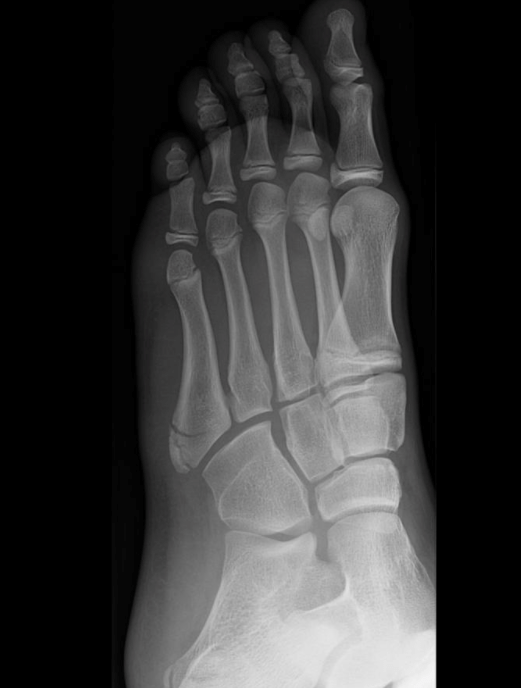

This is a Medial Oblique view of a Left foot

This is a medial oblique view of a skeletally immature patient. An extraarticular cortical break is noted at the base of the 5th metatarsal from lateral distal to proximal medial in a transverse orientation, consistent with an avulsion fracture. The fracture only involves about 60% of the 5th metatarsal and does not transverse the width of the bone. The fracture is nondisplaced in this view. The apophysis is also noted on the lateral aspect of the base of the 5th metatarsal, oriented vertically. This is normal in a skeletally immature patient, as are the other growth plates throughout the foot. No other cortical breaks or dislocations are noted.